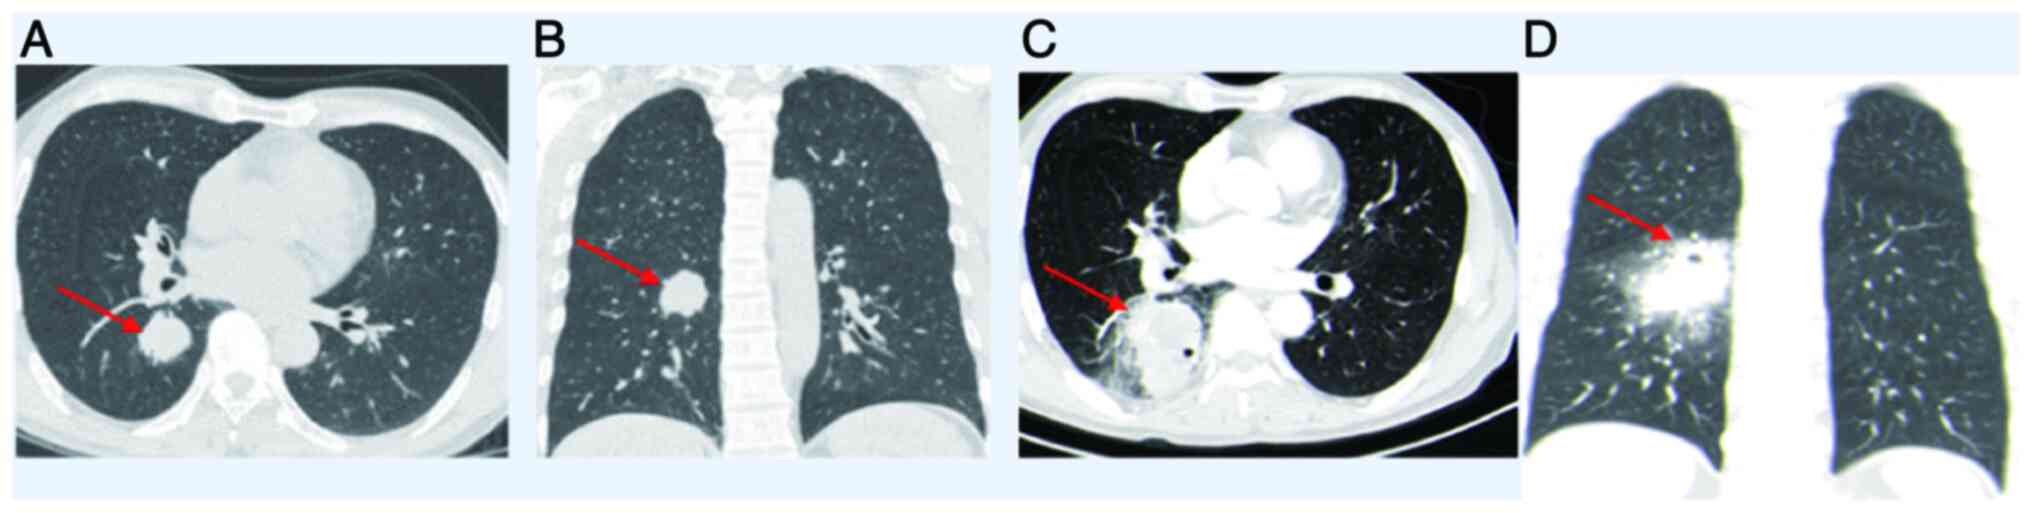

In clinical practice, the management of a lung abscess (LA) usually initiates with antibiotic administration to address the infection. Nevertheless, for cases presenting with refractory pulmonary tumors complicated by a LA, surgical intervention stands as an essential therapeutic recourse. The current study presents case involving lung cancer complicated by a LA. Despite continuously elevated infection marker levels, surgical intervention was promptly performed following the normalization of the patient's temperature. Subsequent postoperative histopathological analysis and immunohistochemistry revealed a moderately differentiated squamous cell carcinoma located in the lower right lung, classified as T2aN0M0, Ib stage. Following a 2‑year follow‑up period, no cancer recurrence was observed and the patient exhibited a favorable prognosis. This case highlights the vital role of surgical timing in the management of lung cancer complicated by an acute LA. Early surgical intervention may play a crucial role in arresting the advancement of lung cancer, indicating that prompt surgery upon temperature normalization could serve as a significant treatment indication for these patients.

Figure 3